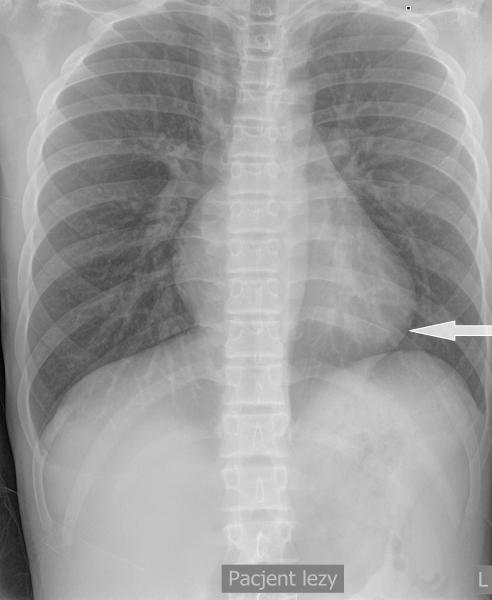

Przypadek 44: U 18-miesięcznego chłopca po operacji przepukliny przeponowej lewostronnej (operacja przeprowadzona po urodzeniu) wykonano kontrolne zdjęcie rtg klatki piersiowej.

Rozpoznanie: Na zdjęciu rtg klatki piersiowej, w okolicy nadprzeponowej po stronie lewej, rzutuje się owalna przestrzeń powietrzna - pętla jelitowa w klatce piersiowej? Podejrzenie nawrotu przepukliny.